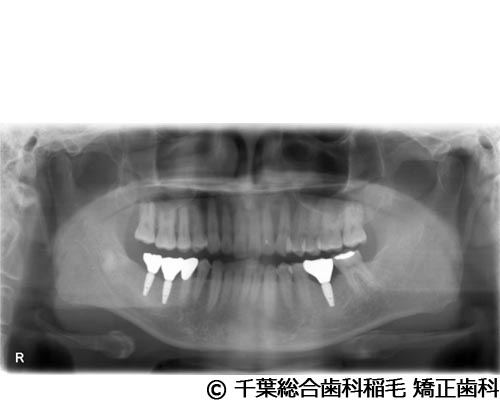

【症例3】上下5本インプラント埋入手術

- 治療前

- 治療後

- 治療名

- 上下5本インプラント埋入手術

- 費用

- 2,500,000円(税込)

- 期間

- 11ヵ月

治療内容

-

患者様の症状

欠損歯が多いため、お食事が取りにくく、インプラント治療のご相談でご来院されました。

治療法

状態の悪かった歯も含め、上下5本インプラントを埋入しました。

治療結果

奥歯でしっかり噛めるようになったと喜んでいただけました。

現在も定期健診で拝見させていただいています。

※治療結果は患者様によって個人差があります。